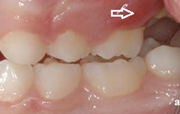

Vali sind huvitav pilt ja me näitame sellega seotud haigust ja sümptomeid